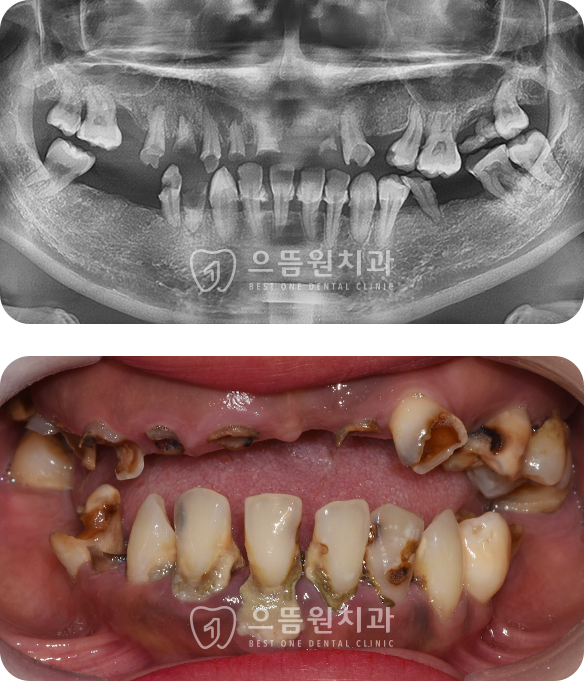

CASE 03

58세 / 남

상악 전체 임플란트, 하악 구치부 임플란트

오랜 시간 잇몸 질환과 충치로 인해 다수 치아 상실한 환자분

초진 당시 식사가 힘든 상황이셨고, 심미적인 스트레스도 많으셨습니다.

상태가 그나마 양호했던 하악 전치부와 소구치를 제외하고

발치후 임플란트로 수복하여 심미성과 기능을 회복하였습니다.

치료기간 : 2024.03.16 ~ 2024.08.14

BEFORE

AFTER